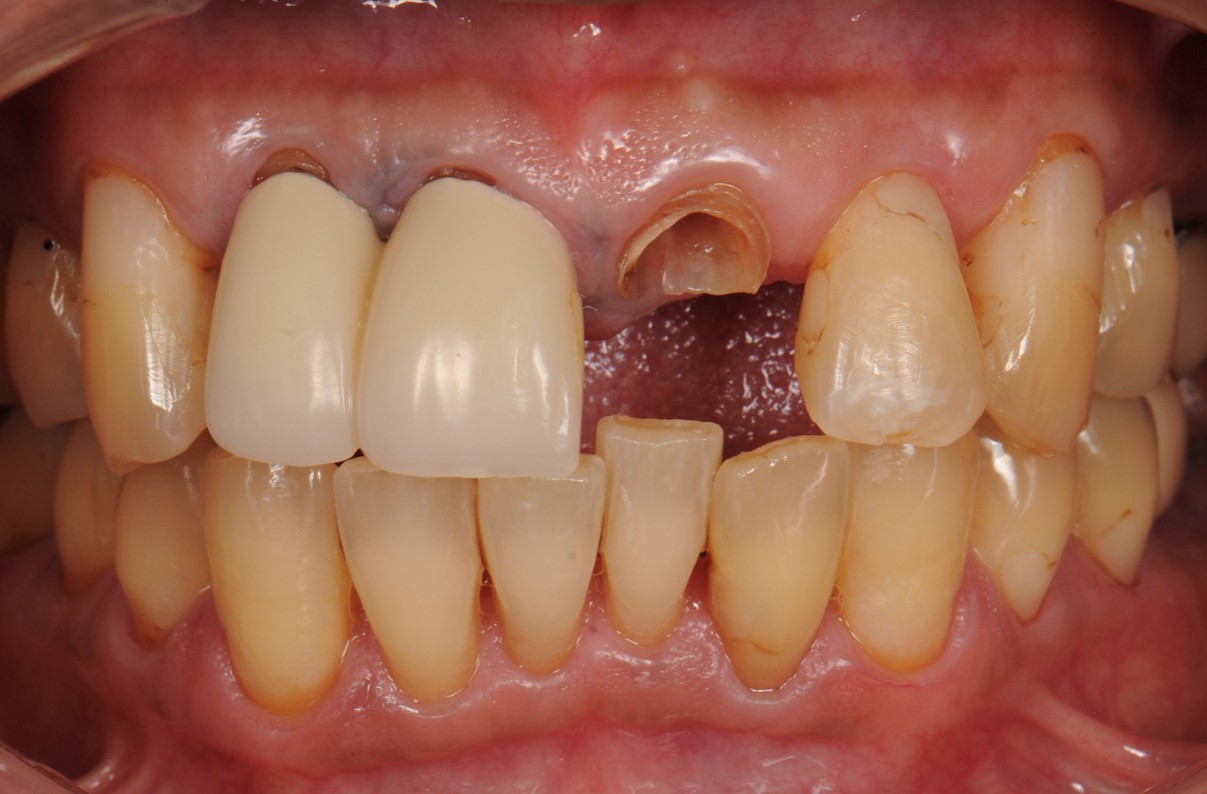

case3 症例(セラミッククラウン・ラミネートべニア前歯)

治療前

| 費用(税込み) | セラミッククラウン:154,000円×4本+ポンティック66,000円 |

|---|---|

| メリット・デメリット | 歯を削る歯質を削合する必要がある |

| 治療回数 | 5-6回(根管治療は別) |

| 主訴 | 歯の形態をきれいにしたい |